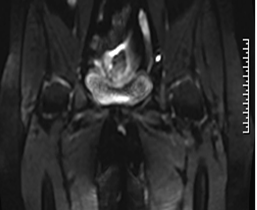

磁共振成像(MRI)能清晰显示子宫及其周围组织的解剖结构,有助于评估异常血管的走行、范围及其与邻近器官的关系,为临床诊断与治疗规划提供重要依据。

(子宫动静脉瘘MRI影像示意图)

典型MRI表现包括:

■ 子宫动静脉瘘MR-T1WI和T2WI序列子宫肌层或宫旁组织中可见卷曲扩张的流空信号,表现为无信号或低信号区域,类似血管的“流空效应”,提示存在异常扩张的血管团;

■ 增强T1WI序列病变部位可见迂曲的血管强化影,显示粗大的动脉血管与引流静脉直接交通,且无连接两者的毛细血管网;

■ 部分患者伴随子宫体积增大,子宫肌层交界区可能破坏,出现锯齿状或不规则的血流相关信号,提示病变累及肌层;

■ MRI可清晰显示动静脉瘘与周围组织(如宫旁血管、膀胱、直肠等)的关系,帮助评估病变范围及是否侵犯邻近器官。